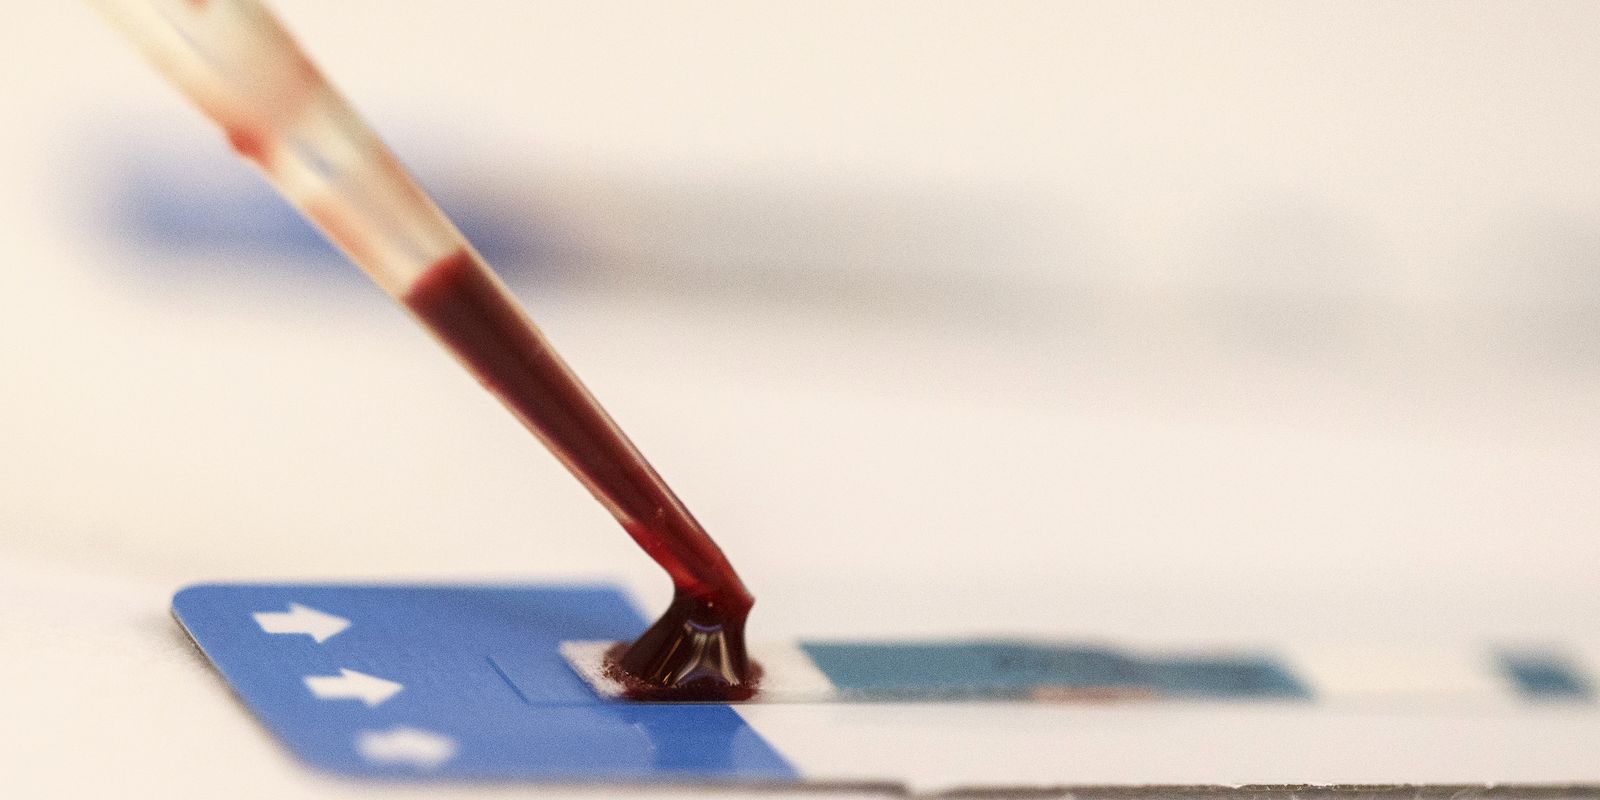

Geralmente, o gatilho para o problema é uma infecção por vírus, mas nem sempre o agente causador é confirmado por exames.

Das principais infecções causadoras de SRAG, três podem ser prevenidas por vacinas disponíveis no SUS: Influenza A, Influenza B e Covid-19.